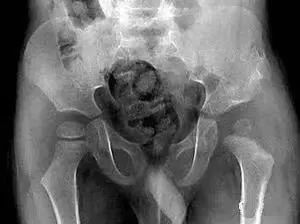

(1)股骨颈骨折

股骨转子间骨折:受伤机制与本病相似,但患者年龄常更大,局部肿胀明显,压痛点在股骨为粗隆部,皮肤一般可见瘀斑;X线片可助鉴别。

(2)股骨转子间骨折

股骨颈骨折:受伤机制与本病类似,但年龄相对较小,局部肿胀及痕斑不甚明显,压痛点在腹股沟中点;X线可助鉴别。

髋关节后脱位:常见于青壮年,有强大暴力损伤史;弹性固定于屈髋、屈膝、内收、内旋位,在臀后可扪及脱出的股骨头;X线片可鉴别。

股骨干上1/3骨折:青壮年及儿童多见,有明显外伤史;局部压痛敏锐,出现短缩、成角或旋转畸形,可触及骨擦感和异常活动;X线片示股骨干骨折。